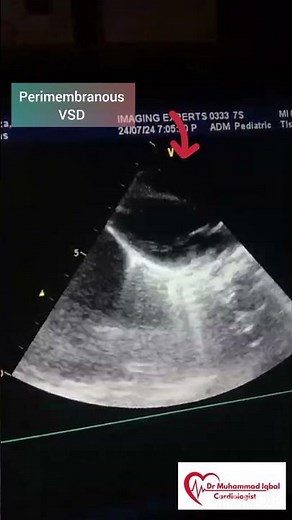

Perimembranous VSD | VSD | congenital heart anomalies | VSD

…

已浏览 568 次

2024年7月27日

YouTube

Cardio Care by Dr iqbal